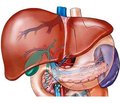

Неалкогольна жирова хвороба печінки: особливості метаболічних змін на різних етапах розвитку хвороби

Степанов Ю.М., Недзвецька Н.В., Ягмур В.Б., Кленіна І.А.

ДУ «Інститут гастроентерології НАМН України», м. Дніпро, Україна

Журнал "Гастроэнтерология" Том 52, №1, 2018